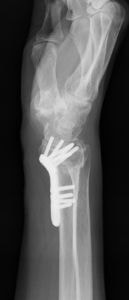

橈骨遠位端変形治癒骨折の術前(左)と術後(右)

遠位橈尺関節の不安定性を伴う尺骨突き上げ症候群に対する尺骨短縮術の術前(左)と術後(右)。術後には関節の不安定性が消失し、疼痛も出現しなくなった。

前腕にある2本の骨:橈骨(とうこつ)と尺骨(しゃっこつ)の長さが有意に異なることによって起こる障害の一つです。尺骨突き上げ症候群は、尺骨が橈骨よりも長いことによって起こる手関節尺側部の障害の総称です。尺骨が橈骨より長いこと自体は悪いことではありませんが、長年の使用により疼痛を生じる原因となる場合があります。尺骨が長くなる原因のほとんどは先天的な素因によるものですが、橈骨の骨折によって生じることもあります。

治療は、症状の原因に対してピンポイントに行うことが原則ですが、尺骨突き上げ症候群においては『どの要素が最も症状に関与しているか?』を見極めることが困難であるため、相当期間の安静を保っても症状が改善しない場合には、すべての要素を同時に治療すべく『尺骨短縮(骨切り)術』を行います。

具体的には、前腕尺側の皮膚切開から尺骨を骨切して短縮し、プレートとスクリューを用いて固定します。しっかりと固定されれば早期から簡単な手の使用は可能ですが、手関節に負荷が掛かる動作・業務・スポーツは、3ヶ月ほど控えていただく必要があります。